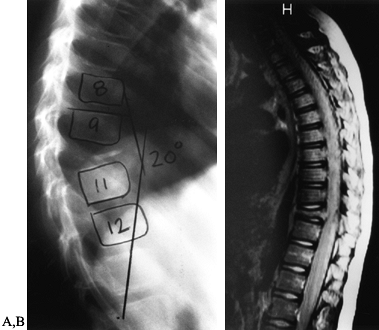

and distinguishes it from other benign bone lesions, including osteoid

osteoma. Osteoblastoma has a predilection for the spine, particularly

the posterior vertebral elements (84). In large

series, up to a third of cases were located in the spine with near

equal distributions in the cervical, thoracic, lumbar, and sacral spine

(112). The second most frequent site of

involvement is the long bones, followed by the bones of the hands and

feet. Pathologic fractures through the lesions have not been reported.

The pain increases in severity with time and has an unpredictable

response to anti-inflammatory agents. Swelling and atrophy of the

affected area may be present on physical exam. When the spine is

involved, the patient often presents with a painful scoliosis and

limitation of motion secondary to paraspinal muscular spasm. The lesion

is usually located at the apex of the concavity of the curve (112).

The scoliosis usually resolves following removal of the offending

lesion. Persistent structural deformity may ensue if there is a

significant delay in diagnosis. Neurologic deficit as the presenting

complaint is not uncommon with spinal lesions. While the symptoms are

typically mild, severe neurologic compromise has been reported (117).

osteoblastoma. Standard biplanar radiographs are typically capable of

detecting lesions outside the sacrum. They reveal a round osteolytic

lesion often greater than 2 cm in diameter, containing varying amounts

of internal mineralization and surrounded by reactive bone. The lesions

may be intramedullary, but the majority are intracortical. In addition,

osteoblastomas may arise in the diaphysis, metaphysis, or epiphysis.

When epiphyseal lesions do exist, they most often occur in the hands

and feet. The lesion may expand through the involved cortex, but it

seldom has an associated soft-tissue mass. In the spine, at least 90%

of the lesions involve the posterior elements, namely the spinous

process and arches. Although the

tumor

may extend into the vertebral body, it rarely arises in or exclusively

involves the anterior spine. Details of spine lesions, such as the

extent of mineralization and degree of rim sclerosis, are more easily

discernible on CT scan. As spine lesions are often expansile, CT scan

is superior to plain films in evaluating the relationship of the tumor

to adjacent neurologic structures and for the purposes of staging and

preoperative planning. If evidence of spinal cord or nerve root

compression is apparent, obtain an MRI, as it provides exceptional

imaging of the neural elements. Radionucleotide studies will

demonstrate intense focal accumulation of the isotope. This study is

perhaps most useful to help localize the origin of the lesion in

patients with back pain in whom the diagnosis of osteoblastoma is

suspected. Multicentric involvement has not been reported.